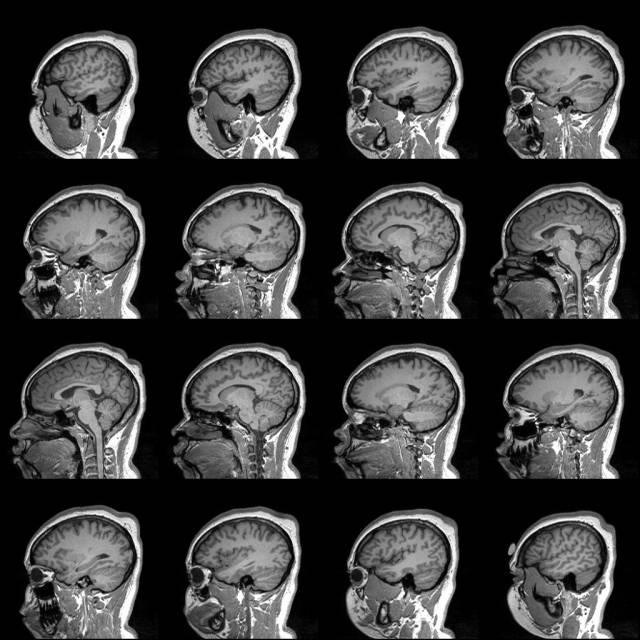

Depending on the sequence using for collecting structural MRI data, the output image sometimes exhibits a noticeable amount of intensity inhomogeneity bias. This is demonstrated in the screenshot below: